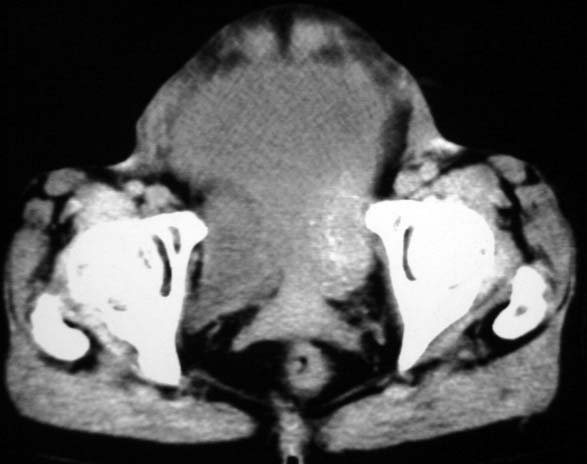

女,75岁,腹部胀大半年余,无其他症状。

考虑来源与卵巢的巨大囊腺瘤或囊肿。

考虑来源于卵巢的巨大囊腺瘤;如果是单纯囊肿不知其前部的更低密度区怎么解释?

考虑来源卵巢巨大黏液性囊腺瘤。